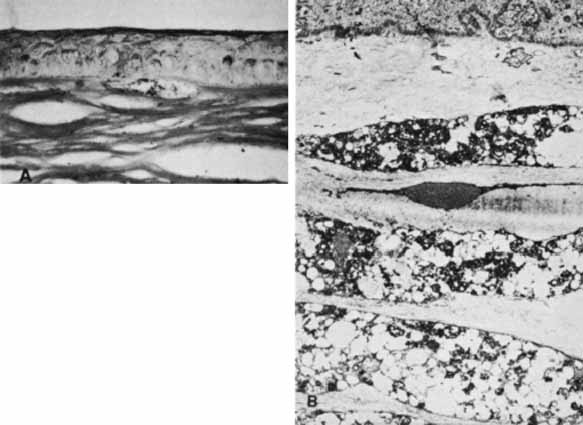

Ultrastructural studies of the cornea in human congenital glaucoma are rare,68 but the ultrastructure in rabbits with spontaneous buphthalmos has been described in detail.69 Intraepithelial and subepithelial edema is present, accounting for the ease with which one can remove the epithelium clinically. Stromal edema, loss of regular collagen architecture, and the degree of scarring correlate with the degree of corneal opacity and thickness. In rabbits with mild to moderate corneal clouding, Descemet's membrane is thicker than normal and manifests the compact structure typical of basement membrane. In rabbits with more severe corneal opacification, a layer of small-diameter collagen fibrils enmeshed in amorphous material appears posterior to Descemet's membrane. In these rabbits, no tears in Descemet's membrane are observed clinically or histopathologically, suggesting that corneal edema may occur from elevated intraocular pressure alone. The thin endothelial cells can be as large as four times their normal size and contain cytoplasmic vacuoles appearing as small pits on scanning electron microscopy. In humans, these enlarged endothelial cells may represent the ones that decompensate later to produce corneal edema. Recently, in vivo confocal microscopy has been used to further evaluate Descemet's tears and endothelial changes associated with congenital glaucoma.70 Key findings include a mild reduction of keratocyte density in the middle and posterior stroma, along with the presence of discontinuous hyperreflective structures overhanging the endothelial layer at the level of Descemet's membrane. Additional confocal analysis of the endothelial layer demonstrate a low cell count, focal cellular lesions, severe polymegethism, and pleomorphism.70

All patients with MPS and mucolipidoses in which corneal histopathology has been studied have demonstrated abnormal deposition of storage substrate, even in cases in which they were not clinically evident (Table 4). The hallmark histopathologic findings in these disorders are storage of excess glycosaminoglycan and glycolipid as membrane-bound vacuoles in keratocytes (Fig. 12). The glycosaminoglycans stain blue with colloidal iron and Alcian blue, and the glycolipids are best seen in frozen sections of unfixed tissue. Transmission electron microscopy demonstrates single membrane-bound cytoplasmic vacuoles containing fine fibrillogranular material along with lamellar bodies, likely representing glycosaminoglycans and glycolipids, respectively. These vacuoles can distend the keratocyte to many times their normal size, making them clinically visible as fine punctuate opacities. In more advanced cases, a fine extracellular granular material surrounds the keratocyte and contributes to the gray stromal haze seen clinically.

Fig. 12 Cornea showing subepithelial accumulation of glycosaminoglycan (colloidal iron, ×400). B. Cornea from MPS-VI micrograph shows fibrillogranular material in the cytoplasm of keratocytes (×6000). (courtesy of K. Kenyon, MD)